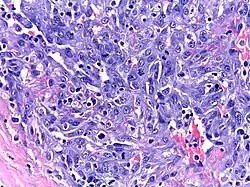

| Micrograph of HHV8-associated Castleman's Disease showing LANA-1 positive lymphoblasts in a regressed germinal center and mantle zone. LANA-1 stain. | |

Formal criteria for the diagnosis of HHV-8-associated MCD have not been published; however, diagnosis requires enlargement of lymph nodes in multiple lymph node regions (typically confirmed with radiologic imaging), histologic changes consistent with HHV-8-associated MCD on biopsy of an enlarged lymph node, and confirmation of HHV-8 infection by LANA-1 lymph node staining or peripheral blood polymerase chain reaction for HHV-8.[6] HIV testing is useful for management, but a positive result is not necessary for to diagnose HHV-8-associated MCD.[2]

Unlike the other subtypes of Castleman disease, UCD and iMCD, which can present with a spectrum of features on microscopic analysis (histology) of tissue biopsied from an enlarged lymph node, only a plasmablastic pattern of histologic features has been described in HHV-8-associated MCD. Plasmablastic features are similar to the plasmacytic features seen in iMCD and UCD, with both demonstrating increased plasma cells in interfollicular spaces. Plasmablastic features are differentiated from plasmacytic features by increased numbers of plasmablasts in follicular mantle zones.[10]

Staining with latency-associated nuclear antigen (LANA-1), a marker for HHV-8 infection, is typically positive.[11]